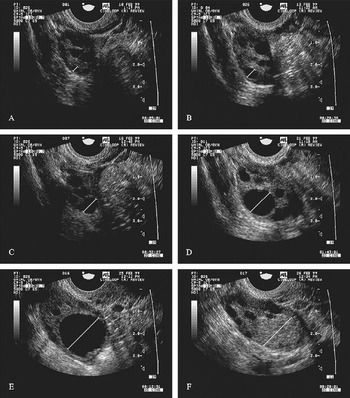

- Transvaginal ultrasound

To ascertain the best timing for IUI, the woman’s ovulation is tracked using transvaginal ultrasound.